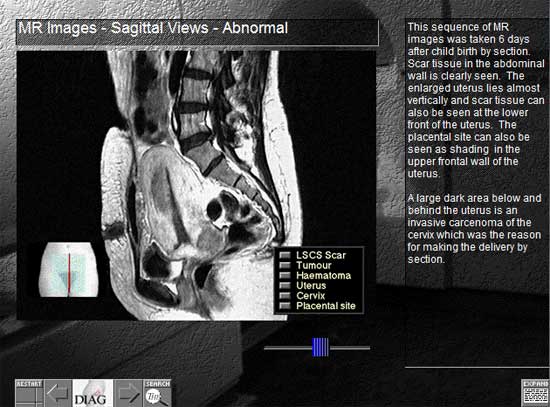

A screenshot of the Cytofocus program showing an MR scanThis was the first interactive project undertaken by the Learning Methods Unit of the Liverpool John Moores University in 1993 and was developed for Cytology departments in hospitals throughout the country. It won a number of prestigious international awards.

I played only a small part in this production but was fortunate enough to work alongside Roy Stringer, a visionary in interactive design